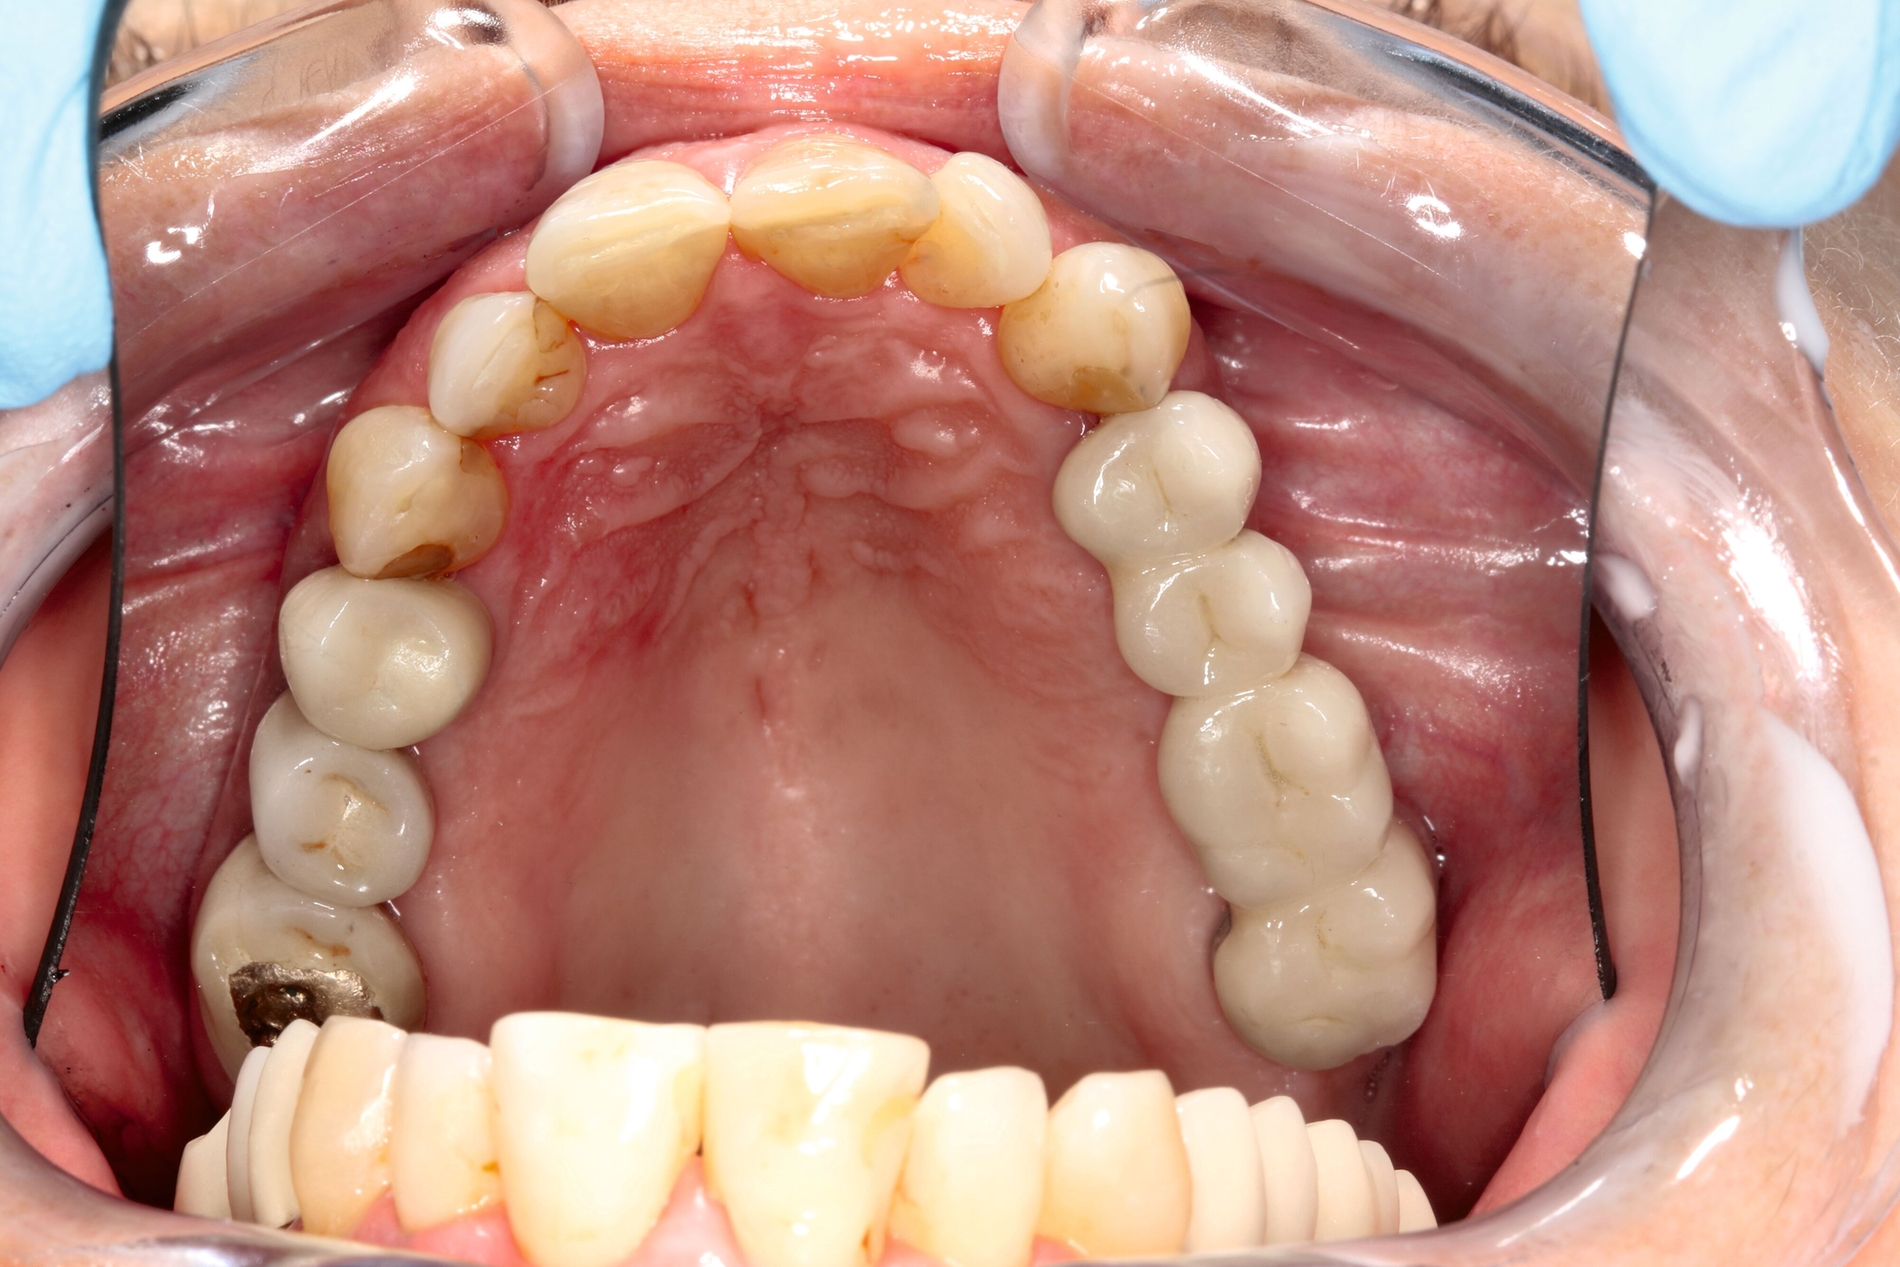

Hier wurde, neben einer klinischen Untersuchung, eine radiologische Diagnostik mittels OPG und DVT durchgeführt (Abbildung 3). Im Ergebnis manifestierte sich der dringende Verdacht, dass die überpresste Wurzelfüllung (Guttapercha-Stift/Sealer) die chronifizierte Pilzinfektion ausgelöst und unterhalten hatte. Daher wurde entschieden, den Zahn 26 zu extrahieren und gleichzeitig das überpresste Wurzelfüllmaterial zu entfernen.

Im weiteren Verlauf wurde die Kieferhöhle durch die Easy-flow-Drainage mehrmals gespült, bis sich klares Sekret über die Nase entleerte. Eine endoskopische Untersuchung der Nase zeigte keine Anzeichen für Pilzreste (Abbildung 4). Unter diesen Umständen konnte der plastische Verschluss der Mund-Antrum-Fistel durch eine Rehrmann-Plastik erfolgen. Die weiteren Kontrollen zeigten einen regelhaften Verlauf der Wundheilung, so dass der Patientin empfohlen werden konnte, eine prothetische Versorgung im zweiten Quadranten durchführen zu lassen.